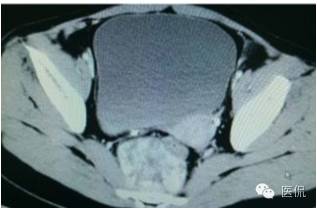

增强延迟期(CT值106HU)

手术是:盆腔占位,病理为:血管肌纤维母细胞瘤。与肛门粘连,于是同时做了肛门的处理。